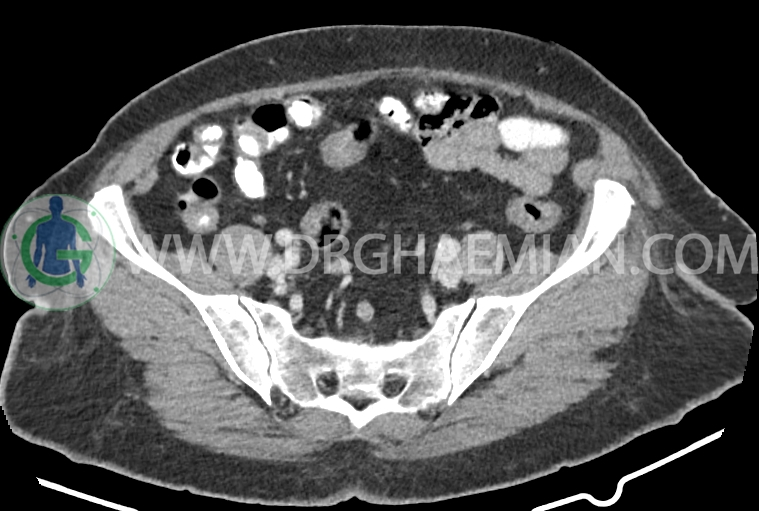

سی تی اسکن شکم و لگن از تششعات برای ایجاد تصاویر عرضی مقطعی از نایحه شکم و لگن استفاده می کند. در این کیس سرطان روده بزرگ، افزایش ضخامت دیواره رکتوم، کلسیفیکاسیون دیواره آئورت و … دیده می شود.

در سی تی اسکن اسپیرال ریه، مدیاستن و شکم و لگن با کنتراست خوراکی و وریدی (مولتی دیدکتور 16 با مقاطع ظریف و بازسازی های ساژیتال و کرونال) :

افزایش ضخامت دیواره رکتوم در ناحیه ای به طول 60mm همراه با نامنظمی سطح سروزال و حدود ده لنفادنوپاتی رژیونال با حداکثر SAD= 10mm

کلسیفیکاسیون دیواره آئورت، شریان های ایلیاک و عروق کرونر

collorectal cancer staging :T4a,N2b,Mx(M0? )

در صورت تایید پاتولوژیک